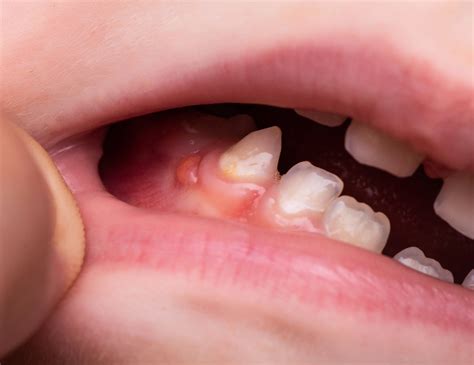

- Encía creciendo sobre el diente (pericoronaritis): En las muelas del juicio a medio salir es común que un colgajo de encía las cubra parcialmente. Si esa encía accesoria se inflama mucho y duele, es señal de pericoronaritis (infección de la encía sobre la muela) y es una señal de alarma.

En adolescentes y adultos jóvenes: La aparición de las muelas del juicio es un proceso natural entre finales de la adolescencia y la juventud. Si la muela del juicio asoma recta y hay espacio suficiente, podría erupcionar sin mayor problema aparte de ligeras molestias. Si la muela del juicio sale parcialmente y notas hinchazón, dolor intenso o que empuja otros dientes, hay que acudir al dentista. El dolor fuerte o inflamación notable no es “normal” y sugiere que el diente está impactado o causando infección (pericoronaritis).

- Cirugía de encía (operculectomía): Si el problema es que la encía cubre parcialmente al diente y se inflama (como en la pericoronaritis de una muela del juicio parcialmente erupcionada), una solución menor es realizar una operculectomía. Consiste en recortar y remover ese colgajo de encía que está sobrando sobre el diente, dejando el diente descubierto.